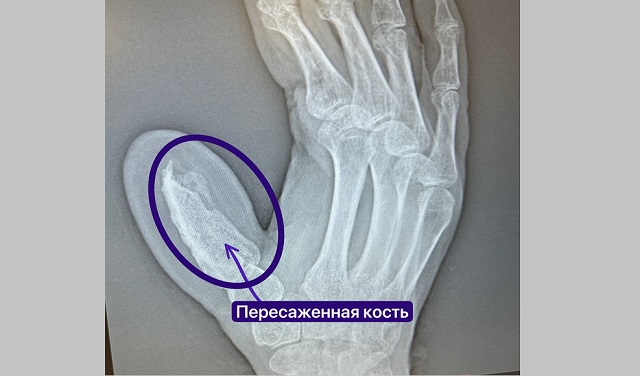

Доктора запланировали плановую госпитализацию и отправили пациента за направлением и сбором анализов. Первым этапом мужчине пересадили пятисантиметровую кость с гребня подвздошной кости вместе с артерией огибающей подвздошную кость и подшили руку к животу, чтобы обеспечить кровоснабжение будущего пальца.

Мужчину около четырех часов оперировали в отделении травматологии №2 микрохирурги Руслан Радьков и Эльвира Кадырова. Следующие полтора месяца пациент ожидал, пока кость приживется, адаптируясь к жизни с некоторыми ограничениями.

«Чаще всего, пациенты не соглашаются на такие операции, потому что не хотят ходить с рукой, пришитой к животу. А по-другому у кости просто нет шансов прижиться, потому что нет нужного кровоснабжения. Организм попросту рассасывает эту кость. Мы же сделали пересадку вместе с артерией, поэтому питание было достаточным. В целом, операции по выращиванию нового пальца далеко не всегда удаются. У нашего пациента все прижилось, а новая кость срослась с костями кисти», — объяснил Руслан Радьков.